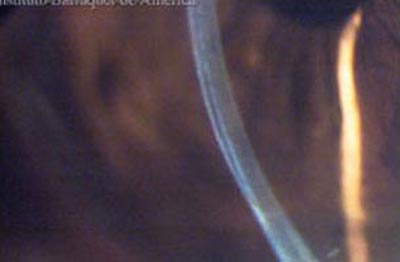

Queratoplastia Laminar Profunda.

Queratoplastia Penetrante

Queratoplastia Laminar

Se realiza cuando el Endotelio no está comprometido en la patología corneal. La técnica quirúrgica es laboriosa, requiere la disección por capas hasta alcanzar la membrana de Descemet; se coloca un injerto al cual se le ha retirado el Endotelio. Las suturas pueden retirarse entre los 3 y los 6 meses de postoperatorio.